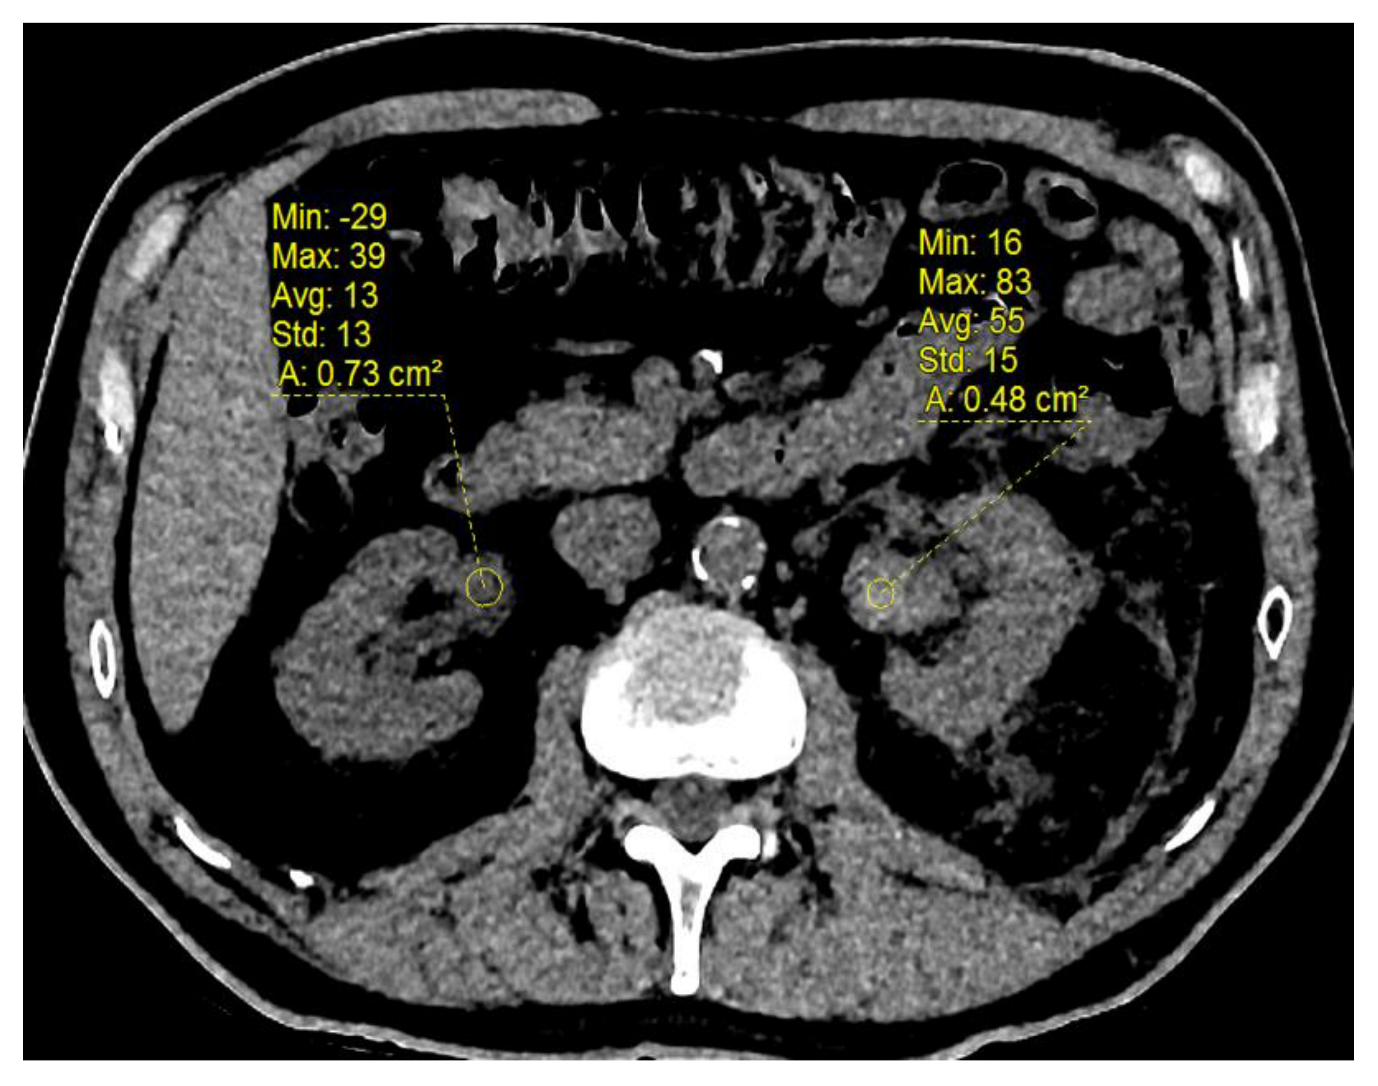

3.4. Change in Renal Functional Volume